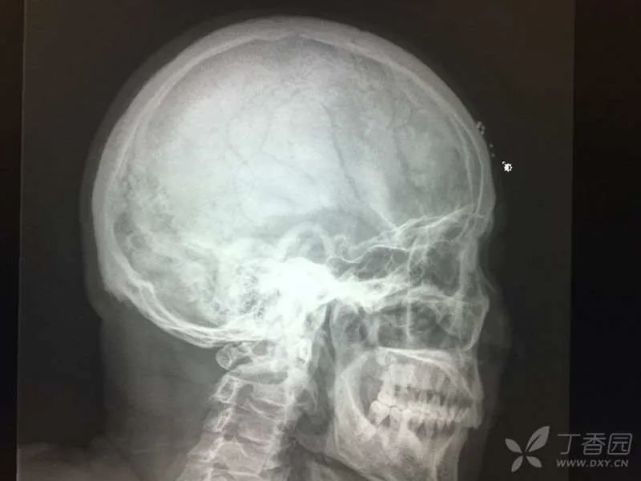

住院期间完善检查结果显示:血常规:WBC 7.4 × 109/L,Hb 62 g/L,PLT 250 × 109/L。尿常规:尿蛋白 3 +,尿隐血 1 +。尿轻链:kap 47.9 mg/L,lam 92.8 mg/L,血轻链:kappa 1.97 g/L,lam 12.2 g/L。生物化学指标:GGT 75 U/L,BUN 18.63 mmol/L,Cr 339 μmol/L。免疫球蛋白:IgA 0.45 g/L,IgM 0.397 g/L。免疫固定电泳:IgG 弱阳性,L 阳性。血清蛋白电泳:Alpha1 5.1%,Alpha2 12.5%,M 蛋白:弱阳性。上腹部彩超:肝光点密集稍粗,胆囊壁毛糙,脾大(21.9 cm × 5.3 cm)。心脏彩超示:左室室壁运动不协调,左室心肌增厚,左房增大,二尖瓣少量返流,主动脉瓣增厚伴少量返流,左室舒张功能减退,微量心包积液,住院期间查头颅正侧位片:额部右侧头皮软组织内多发点状致密影(图 4),颅内未见异常。骨髓细胞学(2015 年 11 月 23 日):增生性贫血、浆细胞比例增高,诊断考虑:浆细胞病待排。2015 年 12 月 22 日再次行骨髓穿刺检查未见明显异常。予输血、促红素等对症治疗后,好转出院。

图片

(图 4 头颅正侧位片)